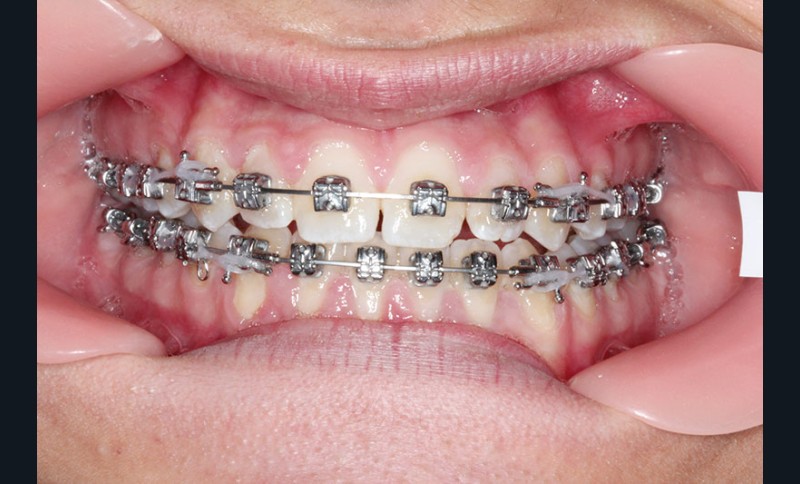

2e phase : mise en place du système multibague Carriere SLX (fig. 7 à 9)

Nous continuons le port des élastiques…